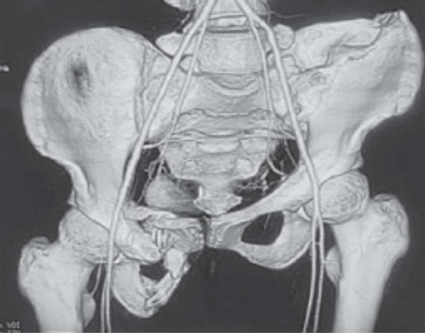

骨盆CT三维重建影像显示骨盆环形状不规则,骨盆明显倾斜(图2)。